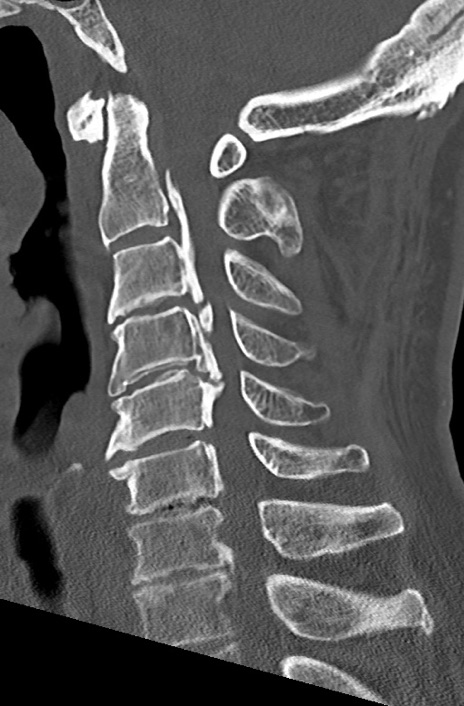

頚椎CT

矢状断像と横断像